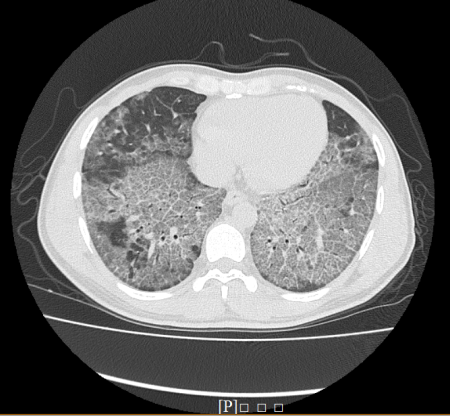

入院查体双肺呼吸音减弱,胸部X线显示双侧弥漫性病变,胸部CT扫描显示双肺广泛磨玻璃影,呼吸空气条件下动脉血气提示存在低氧血症以及轻度二氧化碳潴留,肺功能检查提示存在重度限制型通气功能障碍伴有弥散量重度下降。

我们为患者进行支气管镜肺泡灌洗术,可吸出大量乳白色灌洗液,肺泡灌洗液沉淀物病理检测可见大量嗜伊红染色的分泌物。进一步为患者进行支气管镜冷冻肺活检术,标本病理检测提示肺泡腔内充满嗜伊红染色的分泌物且特殊染色PAS阳性。最终为患者确诊为“肺泡蛋白沉积症(Pulmonary Alveolar Proteinosis,PAP)”。经过肺泡灌洗治疗后患者气促症状改善,复查胸部CT扫描提示双肺病变减轻。

肺泡蛋白症沉积症病人的胸部CT